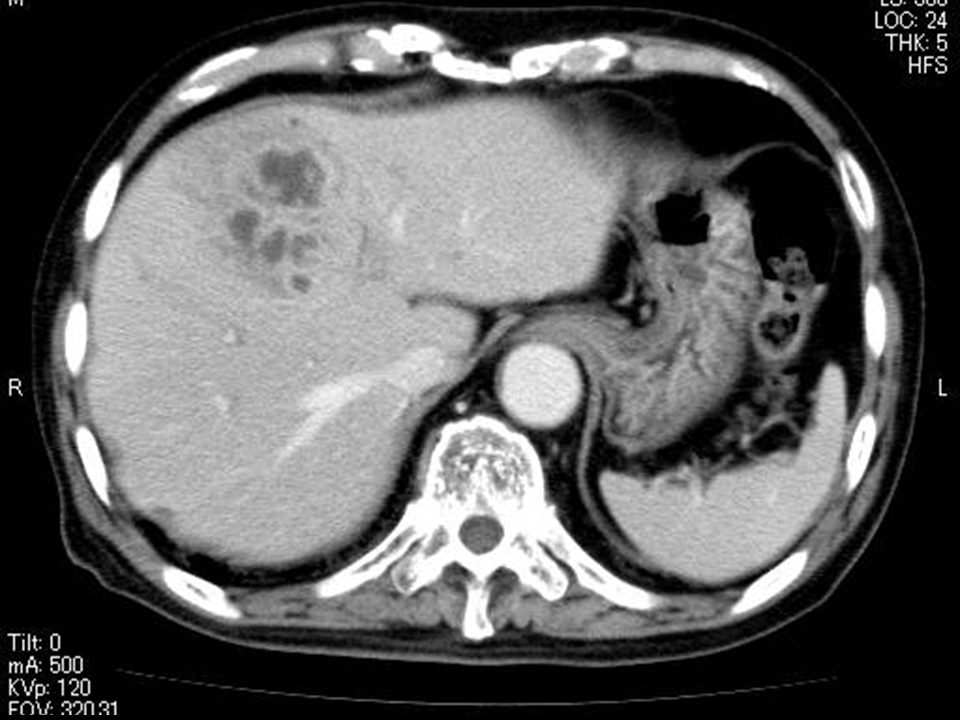

Figure 1 Images of a 76-year-old woman showing a number of MPLPs associated with Klebsiella pneumonia.

A) The post-vascular phase of perfluorobutane-enhanced ultrasonography. B) Contrast-enhanced CT scan. Both (A) and (B) show images obtained before treatment. These images demonstrate the enhancing intricate septation of the MPLP, which exhibits a honeycomb-pattern (arrows).C) Contrast-enhanced CT scan obtained 4 weeks after the antibiotic introduction shows marked improvement of the MPLPs.

MPLP denotes multilocular poorly liquefied pyogenic liver abscess.